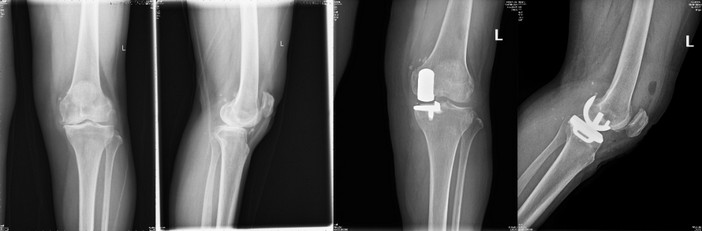

手术治疗

蔡××,女,61岁,单侧膝关节骨关节炎行膝关节单髁置换术,术后第2天即下地行走。